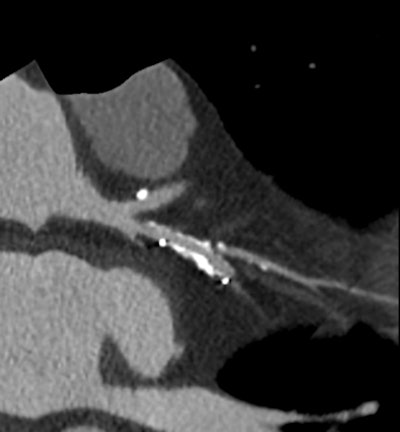

High-definition cardiac CT image obtained on GE Healthcare's Discovery CT750 HD shows stenosis adjacent to stent. (Provided by GE)

With its latest technology on display here in Vienna, GE Healthcare aims to tackle some of the specific challenges faced in conducting CT examinations on cardiac patients, including coronary motion, high heart rates, plaque composition, and accurate perfusion. Its Discovery CT750 HD Freedom Edition offers capabilities that could "change the rules" of cardiac CT. Based on the FREEdom (Fast Registered Energies and ECG) technologies, the system is designed to offer major innovations, including intelligent motion correction, improvements in calcium visualization, plaque material composition assessment, and more accurate perfusion calculations.